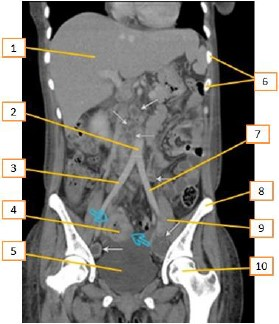

Tomografia computadorizada é um procedimento não invasivo de diagnóstico por imagem que combina o uso de raio-x com computadores especialmente adaptados. É utilizado para criar imagens detalhadas dos mais variados tecidos do corpo humano. O procedimento é realizado através da emissão de raios X rotacionada ao redor do corpo, que, por sua vez e de forma variada, a depender de cada tecido, atenua o feixe de raios-X, que são absorvidos por detectores de radiação, que enviam então os dados para um sistema computacional. Esse sistemconsegue transformar a radiação, através de seus detectores, em um sinal digital no qual se tem a imagem formada muitas vezes mais fidedigna que as imagens radiográficas. Entre os vários assuntos que devem ser conhecidos, a anatomia é fundamental.

Com base no texto acima e de acordo com a região anatômica apresentada, os números que aparecem na imagem estão corretamente descritos em